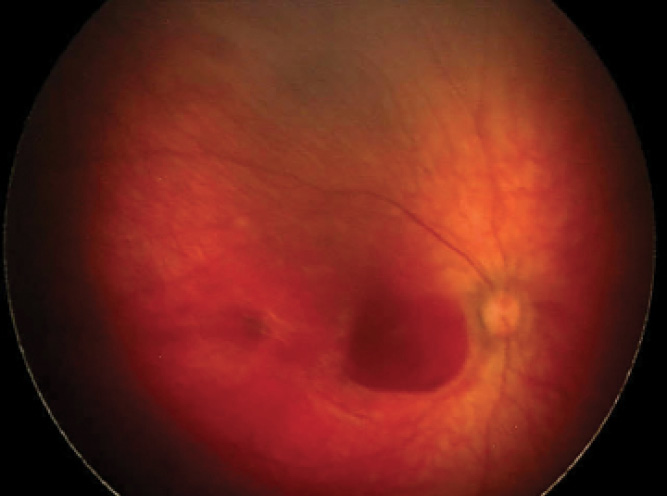

The finding of numerous bilateral retinal hemorrhages involving several layers of the retina or vitreous should make one suspicious of abusive head trauma, also known as nonaccidental trauma (Figure 2).1,2

It is important to collaborate with other services, such as social services, and to ensure that the infant is stabilized. When nonaccidental trauma is suspected, images of the retina should be taken to document the trauma.

Figure 2. Posterior retina of left eye shows numerous hemorrhages in an infant with abusive head trauma.

Figure 3. Persistent subhyaloid hemorrhage in right eye of infant following abusive head trauma.

Persistent subhyaloid hemorrhage over the macula (Figure 3) can be amblyogenic or lead to development of myopia. If the hemorrhage settles inferiorly, out of the visual axis when the infant is upright, it may be possible to prop the infant upright while he or she is awake and delay or even avoid surgery. A lens-sparing vitrectomy to remove vitreous hemorrhage and release subhyaloid hemorrhage may be considered if the hemorrhages do not clear.